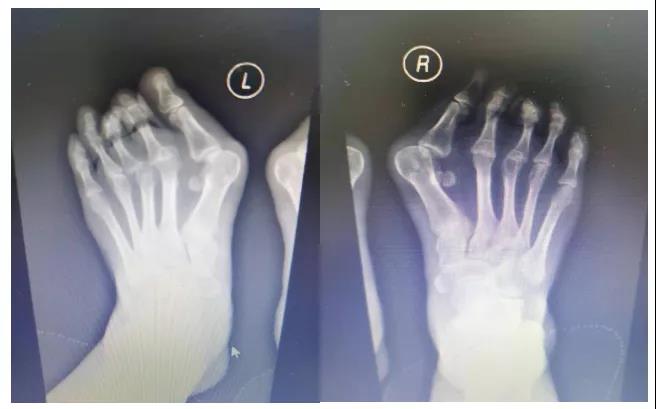

踇外翻截骨矫形

术前X片